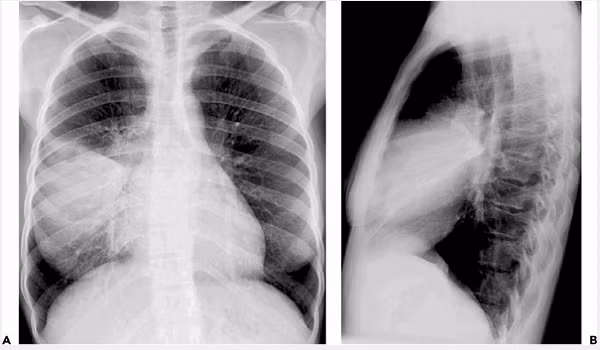

Hình ảnh đông đặc phổi điển hình của bệnh nhân. Đây được xem là "sát thủ thầm lặng" của bệnh nhân COVID-19.

Đối với đại dịch COVID-19 qua các báo cáo, nghiên cứu, khám nghiệm tử thi của bệnh nhân đều cho thấy phổi của họ có biểu hiện của đông đặc phổi cấp và tử vong vì suy hô hấp cấp. Đây được xem là "sát thủ thầm lặng" của bệnh nhân COVID-19.

Không phải bất cứ ai nhiễm virus cũng đều có triệu chứng và tổn thương phổi. Tuy nhiên, nghiên cứu có khoảng 25% bệnh nhân khi nhiễm virus, đầu tiên là virus Sars-CoV-2 xâm nhập tế bào, hình thành nên ổ virus; tiếp theo là gây rối loạn hệ miễn dịch (ví dụ hội chứng bão cytokine); và cuối cùng là gây tổn thương phổi trong đó có đông đặc phổi hay còn gọi là gan hóa phổi.

Hội chứng đông đặc phổi bắt nguồn từ nhiều nguyên nhân khác nhau, có thể là biểu hiện của bệnh lý nào đó về phổi. Để hiểu rõ về tình trạng bệnh của mình, những người mắc đông đặc phổi hoặc nghi ngờ mình bị đông đặc phổi cần trải qua các bước thăm khám mới có thể xác định được bệnh chính xác.

Đối với hội chứng đông đặc phổi cấp tính đa phần người bệnh đều khó phục hồi và chỉ 10 % có khả năng phục hồi lại sau quá trình chạy tim phổi ngoài nhân tạo do hội chứng đông đặc phổi cấp. Nếu bệnh nhân may mắn không chết, phổi của họ cũng bị tổn thương vĩnh viễn, bác sĩ Nam cho biết.